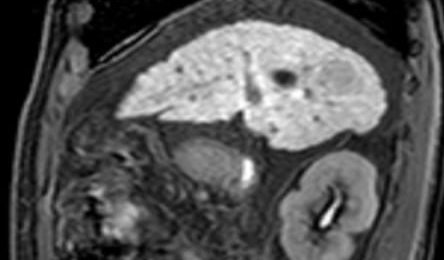

Según el Dr. José Alberto Briceño Polacre, Past President de la Sociedad Venezolana de Radiología y Diagnóstico por Imágenes (SOVERADI), el esquema tradicional para detectar una lesión hepática según las guías norteamericanas, mencionan como estudio inicial a el ultrasonido, luego la tomografía y por último la resonancia. Sin embargo, ahora con la posibilidad de tener un contraste específico, se pudiera realizar como estudio inicial la resonancia magnética con contraste hepato específico, como mejor opción inicial permitiendo diagnóstico oportuno, ahorrando tiempo y recursos.

“Para la resonancia magnética los contraste que se usan habitualmente son los extracelulares y ahora tenemos este nuevo que es específico para el hígado, el contraste órgano específico. La ventaja es que a través del ácido Gadoxético se pueden detectar lesiones más pequeñas y de forma precoz, algo muy importante en el tratamiento del cáncer”, resaltó el galeno.

En Bolivia, existe el acceso al Ácido Gadoxético de la mano de Bayer, este medio de contraste paramagnético de distribución dual (extracelular y hepatobiliar) que permite obtener imágenes por Resonancia Magnética del hígado y de la vía biliar.

En los últimos años, numerosos estudios han demostrado la eficacia del ácido gadoxético en la detección y caracterización de lesiones hepáticas como ser el Cáncer de Hígado mediante RM. “Tener disponible este contraste hepato específico en Bolivia hace que nuestra medicina este al mismo nivel de cualquier otro país. Al tener esto disponible aumentará la sensibilidad y especificidad para el diagnóstico y seguimiento de patología hepática por parte de los resonadores instalados en el país”, añadió Briceño.